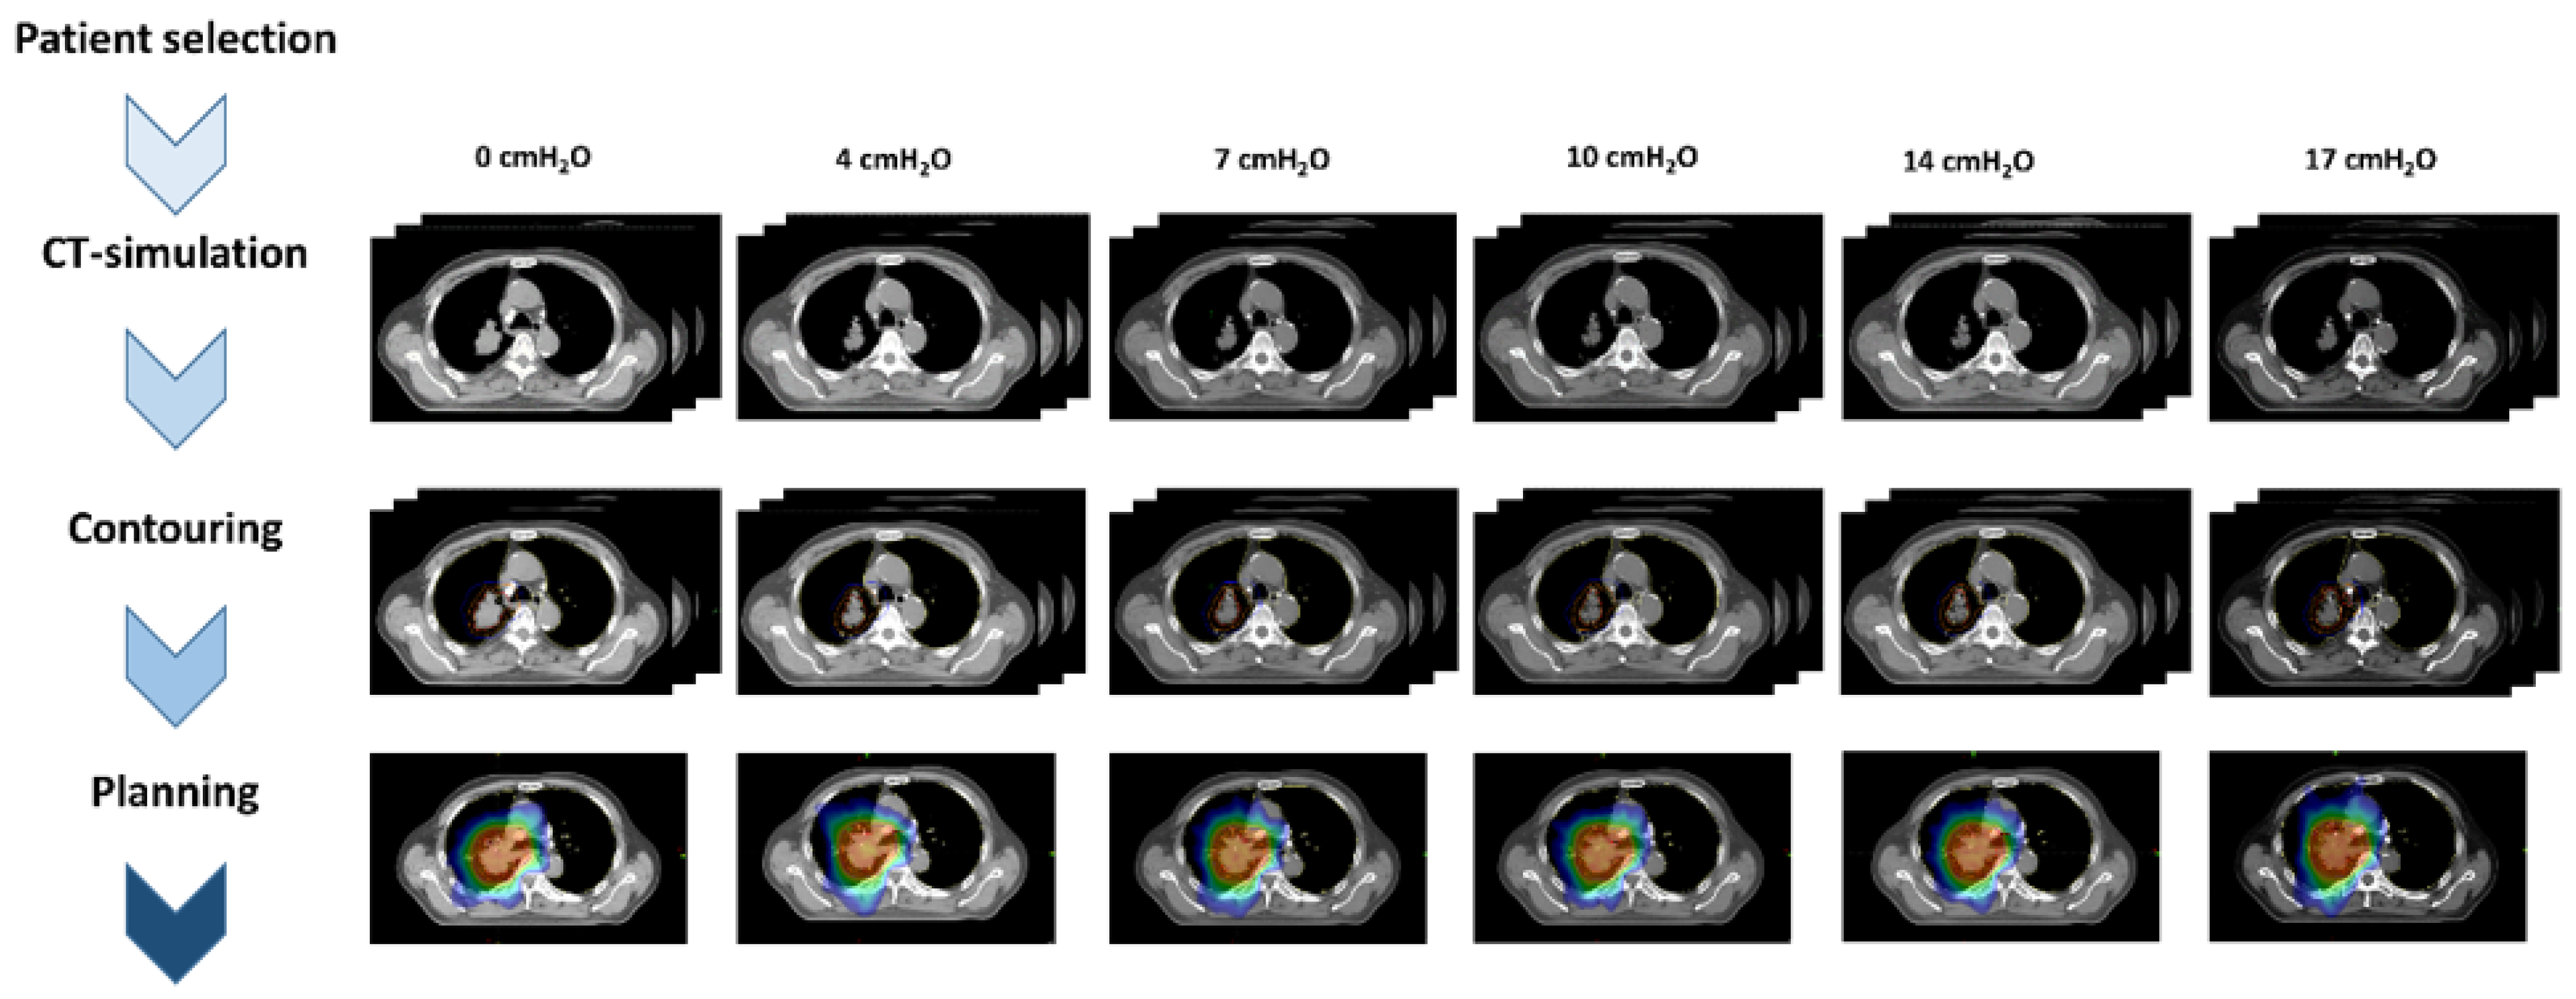

2.2. Application of CPAP on CT-Simulation

2.3. Contouring and RT Planning